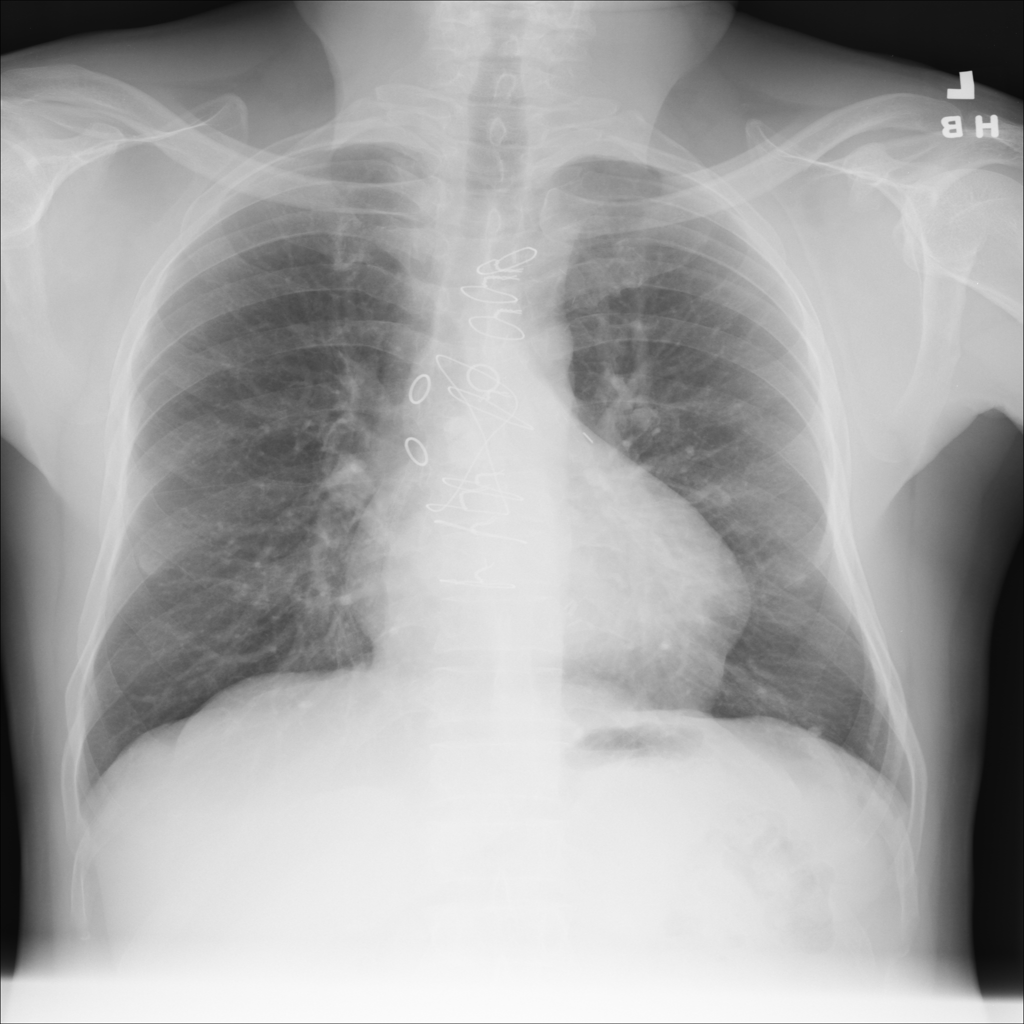

Nodule

A nodule is a small rounded opacity in the lung or chest field. It is a descriptive imaging finding that can be benign or more concerning depending on size, appearance, and context.

Showing up to 90 reference images for Nodule.

PAT-50E5 · IMG-000Nodule

PAT-50E5 · IMG-000

PA